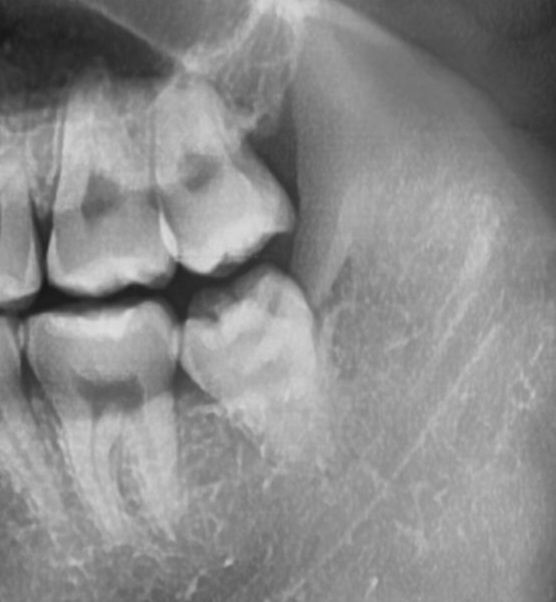

사진은 사랑니 뽑기 전

• 1번 째 사진

• 안녕하세요 치과의사 김철진입니다. 사진상으로 보면 단순 발치엿을꺼 같습니다. 아직 마취가 안풀린게 아닐까 생각되니 너무 걱정하지마세요.

1. 사진상 신경이 사랑니와 아주 가깝진 않습니다.

2. 특별히 발치 중 무리한 기구동작이 없었다면 신경을 건드리진 않았을 것 같습니다.